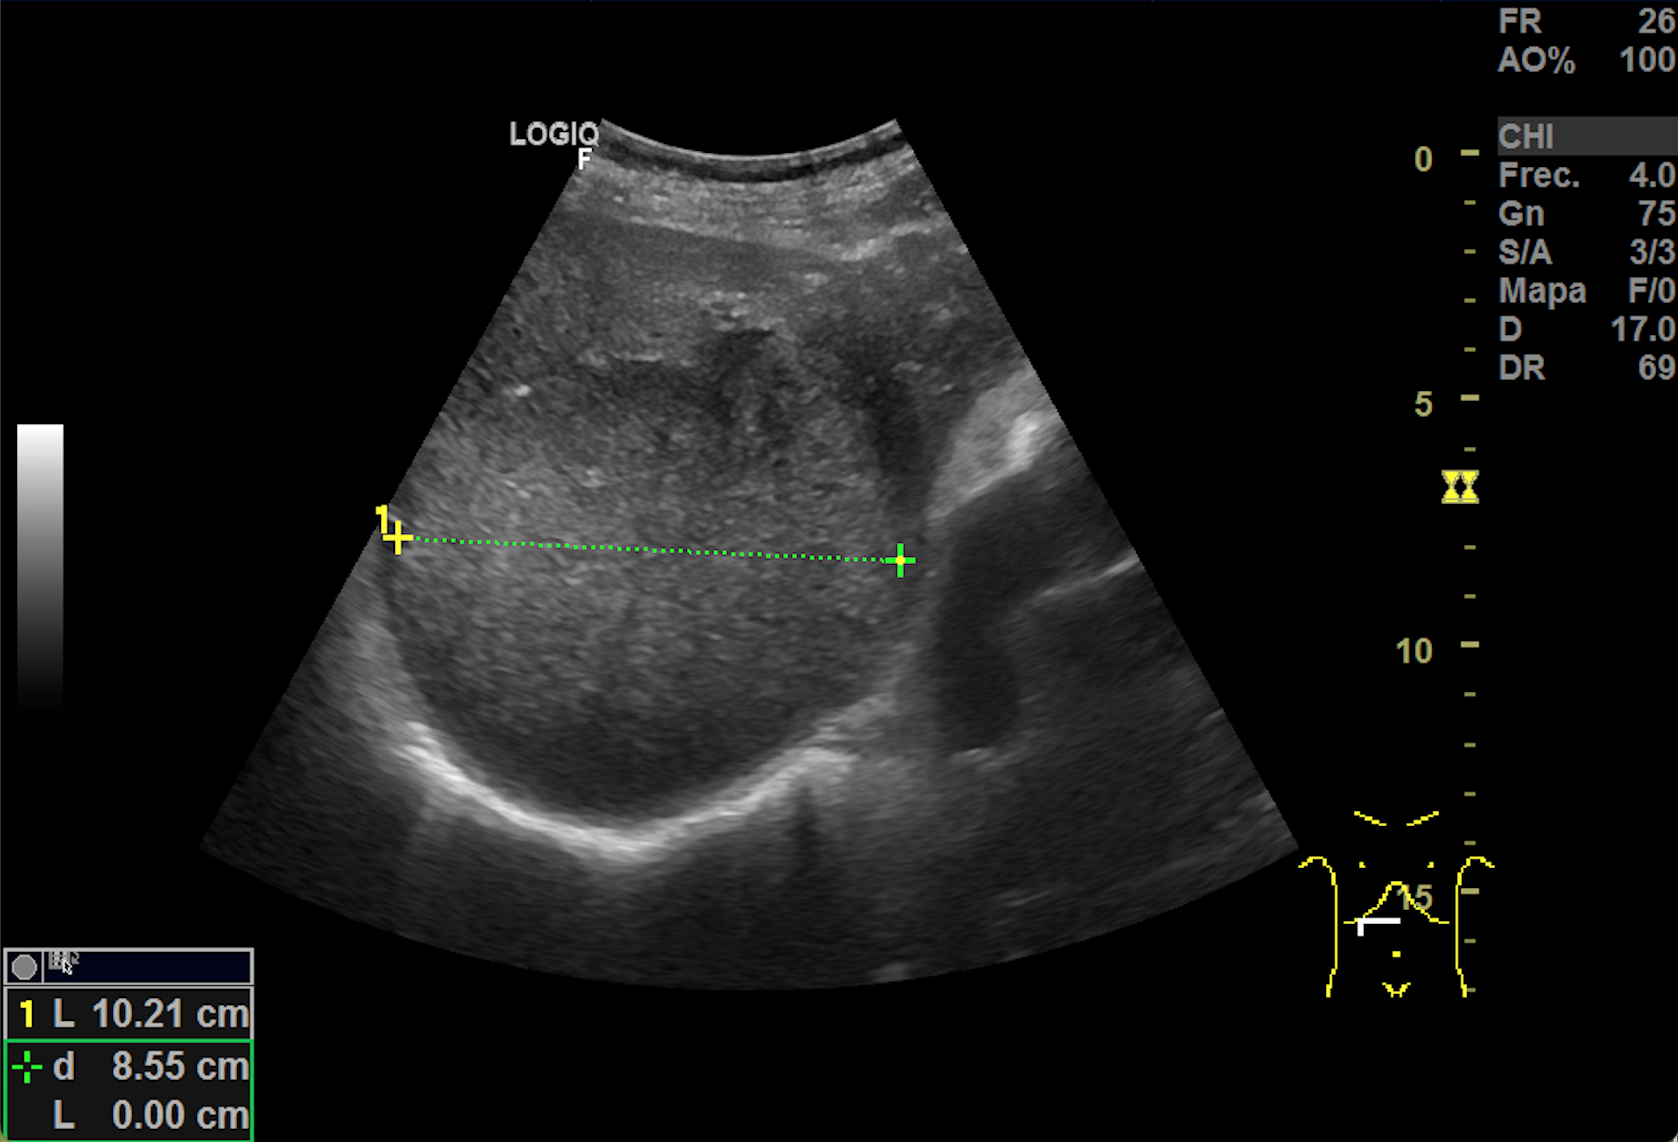

Hallazgos ecográficos

Hígado aumentado de tamaño donde se observan, ocupando gran parte del lóbulo hepático derecho al menos 2 imágenes redondeadas heteroecoicas vascularizadas de hasta 11 cm de diámetro. Vesicula bien replecionada con imagenes heteroecoicas con sombra posterior en su interior. El hemiabdomen izquierdo esta ocupado por lesiones anecoicas que impresionan de quistes renales. No observamos líquido libre.

TAC body: Masa subcarinal que contacta con esófago. Hepatomegalia con 2 lesiones focales de gran tamaño en cúpula de 10 x 12 cm y segmento V-VI de 10 x 7,8 cm. Numerosas adenopatias retroperitoneales y en hilio hepático. Vesicula biliar con colelitiasis. Riñón izquierdo con 2 quiste corticales de gran tamaño (13 cm cada uno).